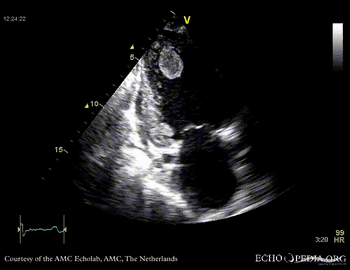

Thrombus in the left ventricle

J. Vleugels, AMC, The Netherlands